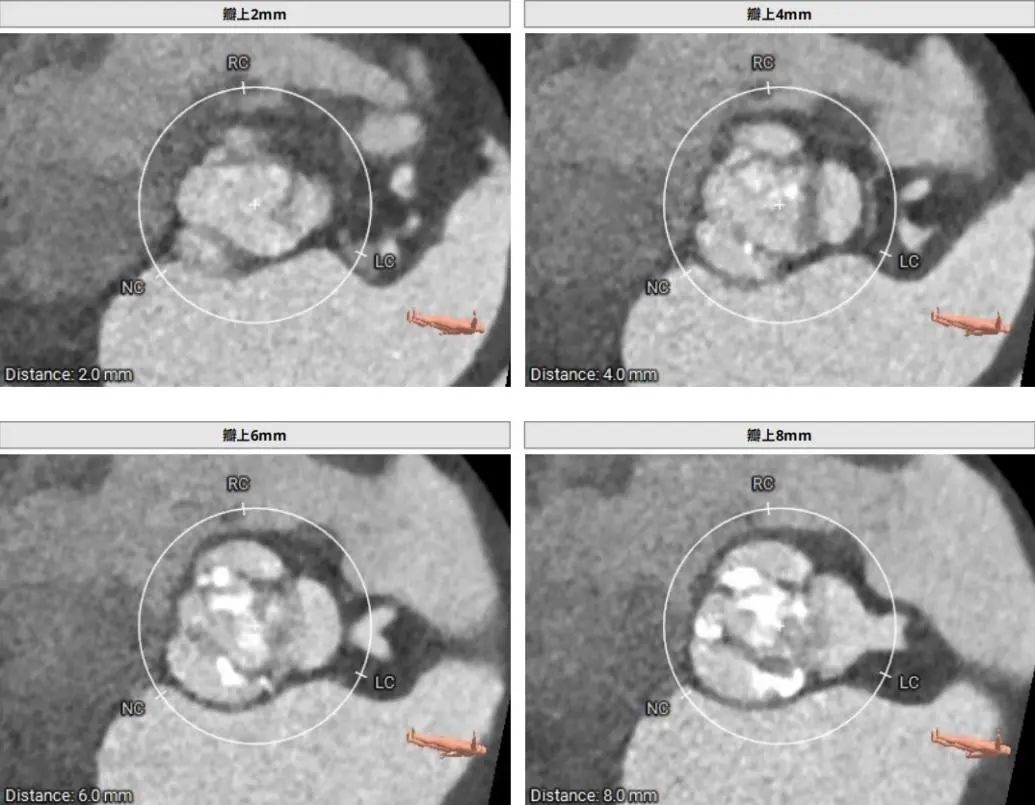

CT术前评估

主动脉根部情况

瓣上2mm--8mm 瓣上结构

左冠高度6.4mm 右冠脉高度12.3mm

♦ 三叶氏主动脉瓣,瓣叶增厚,重度钙化,主要分布于无冠窦及右无瓣叶交界处,瓣膜锚定力充足;

♦ 左右冠脉开口高度分别为6.4mm和12.3mm,左右瓣叶长,冠脉风险高,需球扩时评估是否需要冠脉保护;